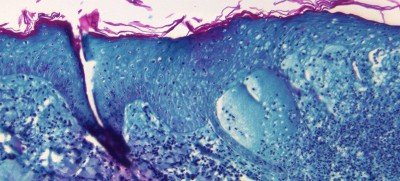

New York: At some point in their life, one in three people will develop some type of neurological disorder – the leading cause of disability and the second leading cause of death, the World Health Organization (WHO) said on Tuesday, launching its first-ever position paper on optimizing brain health across the entire life span.